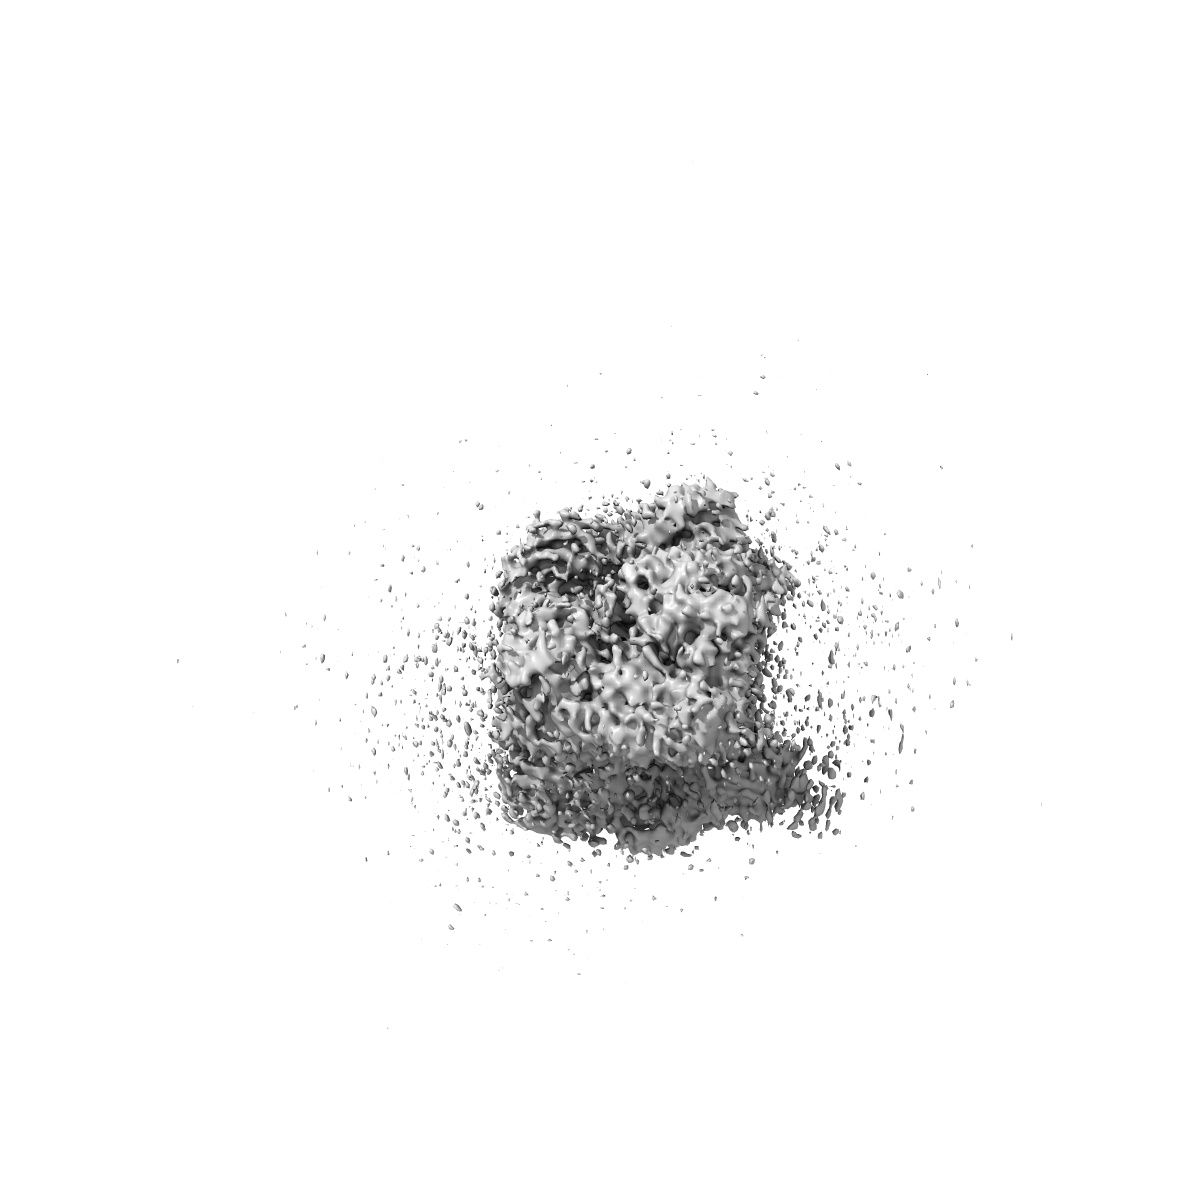

Monkeypox virus DNA replication holoenzyme F8, A22 and E4 complex in a DNA binding form

Sample: Monkeypox virus replication holoenzyme F8-A22-E4 complex with DNA duplex only

Structural basis of human mpox viral DNA replication inhibition by brincidofovir and cidofovir.